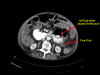

Case presentation: We report the case of an 82-year-old Caucasian woman presenting with a one-day history of generalized abdominal pain, with three episodes of vomiting. An abdominal X-ray displayed multiple dilated loops of the small bowel. A subsequent computed tomography scan of the abdomen and pelvis revealed a thickening of the duodenum and dilatation of the proximal jejunum. Multiple small bowel diverticula were identified with surrounding pockets of free air adjacent to the jejunal diverticula suggestive of a small bowel perforation. Our patient underwent a laparotomy, which identified multiple jejunal diverticula with two pinhole jejunal perforations and associated fecal contamination. The perforations were repaired with primary closure and extensive washout was performed.